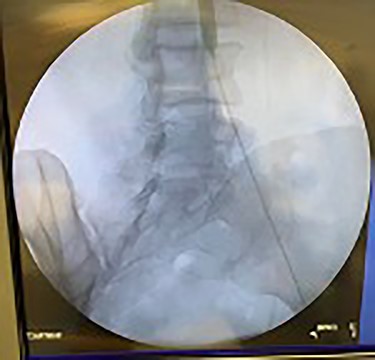

Catheter arteriogram results showed significant occlusion of the left iliac artery (Figs 3 and 4), the right iliac artery (Fig. 1), as well as the distal abdominal aorta (Fig. 2). There were numerous collateral vessels noted, indicating the presence of long-standing proximal stenosis (Fig. 1). The decision was made to use angioplasty to help widen the areas of stenosis. An 8 mm × 40 mm Passeo balloon was advanced from the right femoral artery into the left iliac artery (Fig. 7) and insufflated to 6 mmHg (Fig. 6). The balloon was allowed to remain expanded for 1 min and then was deflated. Next, the distal aorta was repaired in a similar fashion. The balloon was advanced into the distal aorta from the right femoral access and insufflated to 12 mmHg (Fig. 8). The balloon was allowed to remain expanded for 90 s.

Fluoroscopy showing dilation of the distal aorta post-angioplasty.